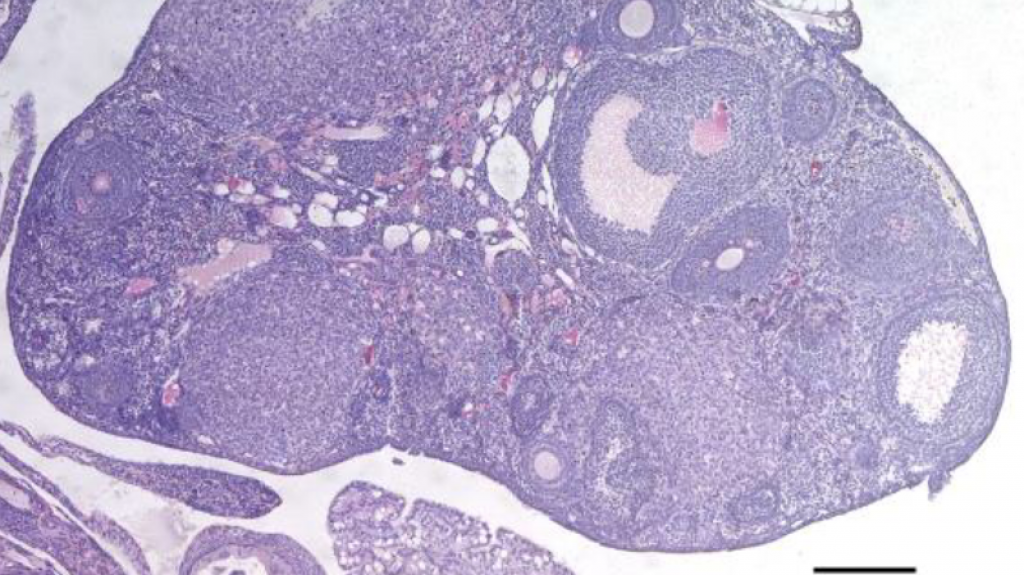

Las mujeres nacen con todos los óvulos que tendrán a lo largo de su vida y estos se van perdiendo progresivamente con la edad, lo que se conoce como envejecimiento reproductivo. Así, la menopausia se produce una vez han desaparecido la mayoría de estos óvulos, a pesar de que la fertilidad natural disminuye sustancialmente antes.

El examen de unos 13,1 millones de variantes genéticas permitió identificar 290 vinculadas al envejecimiento ovárico, de las que muchas están relacionadas con procesos de reparación del ADN.

Y es que los mecanismos que controlan la calidad del ADN y regulan cómo se repara este cuando hay un daño son muy importantes para el mantenimiento del número de óvulos y la fundación ovárica, añade Roig, quien recuerda que la menopausia está asociada con la disminución de la cantidad de óvulos, así que cuanto más permanezcan estos en los ovarios más tarde llegará el cese de la menstruación.